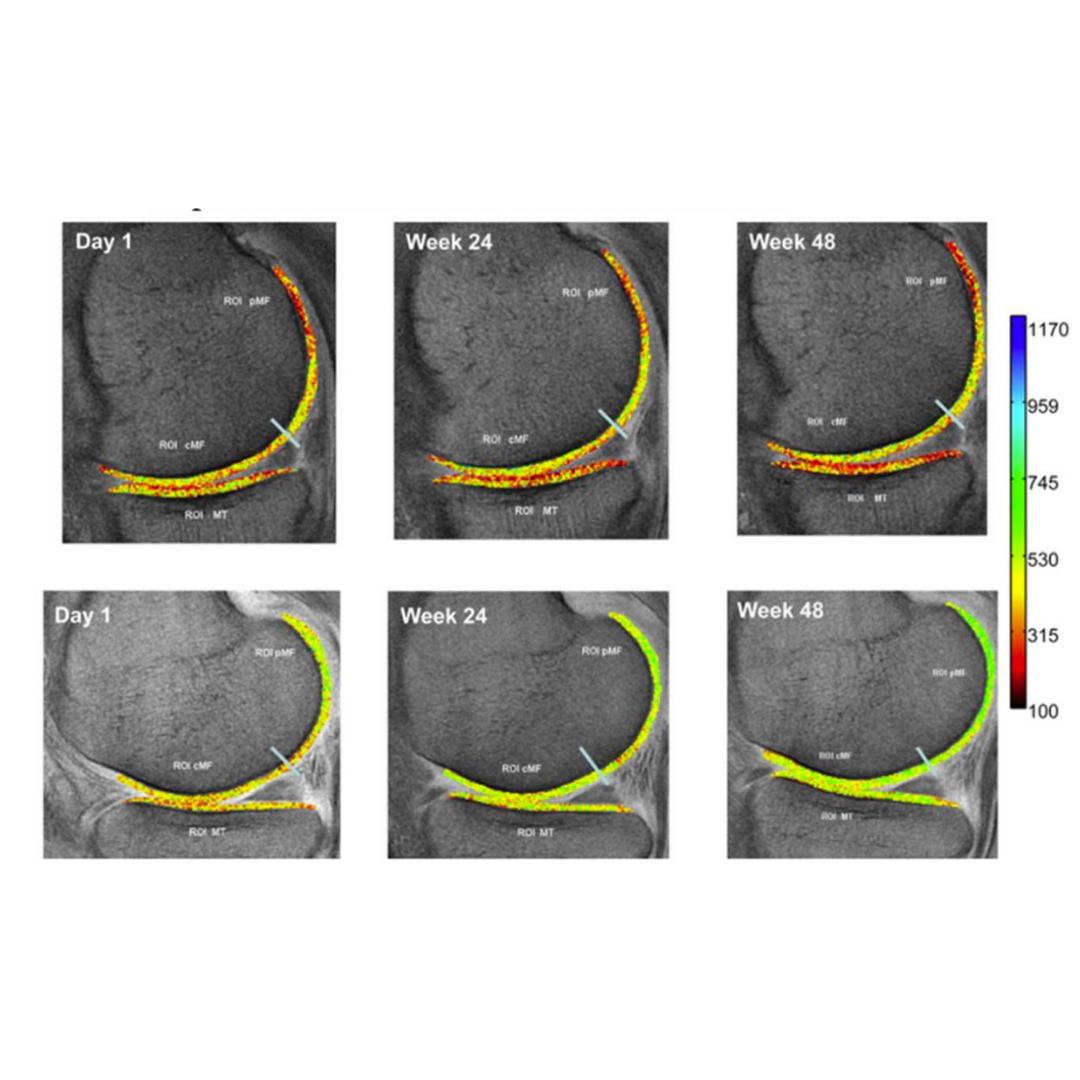

再生影像實證 📊 生效影像記錄

持續補充 48 週,影像顯示原本需關注區域逐漸回歸健康狀態(綠色區域)。